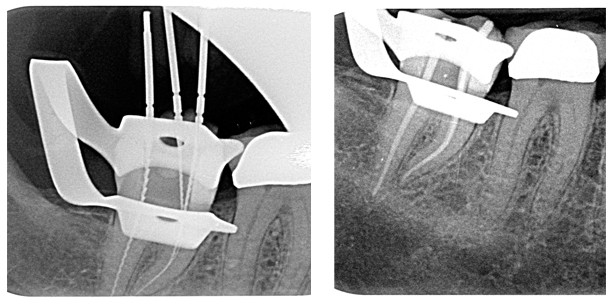

Am 13.05.2013 erfolgte zunächst ein präendodontischer adhäsiver Aufbau an Zahn 47 mesial. Nach Lokalanästhesie und Anlegen des Kofferdams wurde der Zahn eröffnet und die Pulpakammer von Medikamentenresten gereinigt. Zur Darstellung der Kanaleingänge verwendete ich Rosenbohrer für die Isthmuspräparation (H1SML, Komet). Dabei wurde ein geradliniger Zugang zu den Kanälen geschaffen. Darauf folgte die Erweiterung der Kanaleingänge mit Gates-Glidden-Bohrern. Die Pulpakammer und Kanaleingänge wurden zwischen den einzelnen Arbeitsschritten immer wieder mit Natriumhypochlorid 1 % gespült. Im nächsten Schritt wurden die Kanäle nacheinander mit C-Pilot-Feilen (Fa. VDW) sondiert und die Länge endometrisch bestimmt (Root ZX, Fa. Morita) Die nachfolgende Röntgenmessaufnahme (Abb. 2) zeigte die Referenzpunkte und die apikale Situation nicht vollständig. Auf eine Wiederholung der Röntgenmessaufnahme wurde verzichtet. Die endometrischen Werte wurden jedoch nochmals überprüft und die Arbeitslängen schließlich festgelegt.

Abb. 2: Röntgenmessaufnahme Zahn 47.

Die Kanäle wurden mit Papierspitzen getrocknet und die Guttaperchapoints in Größe 35.04 angepasst, sodass diese auf Arbeitslänge leicht klemmten (sog. „tug back“). Zur Kontrolle der vollständig aufbereiteten Kanäle wurde eine Masterpointaufnahme angefertigt (Abb. 3). Die Wurzelfüllung erfolgte dann mit den angepassten Masterpoints und dem Sealer AH+ (Fa. DENTSPLY). Da die Kanaleingänge initial mit Gates-Glidden-Bohrern erweitert wurden, füllten die Guttaperchapoints den oberen Kanalanteil nicht aus, sodass hier die alleinige Einstiftmethode für die Wurzelfüllung nicht infrage kam. Daher wurde die Guttapercha im oberen Kanalanteil mittels Hitzeträger abgeschmolzen und mit einem passenden Plugger die noch warme Guttapercha im Kanal nach apikal kondensiert. Der koronale Kanalabschnitt wurde anschließend bis kurz unterhalb der Kanaleingänge mit warmer Guttapercha aufgefüllt. Die Pulpakammer und die Kanaleingänge wurden abschließend versäubert und der Zahn adhäsiv mit Komposit verschlossen (Scotchbond, Fa. 3M ESPE & Venus Pearl, Fa. Hereaus). Am Ende der Behandlung wurde eine Kontrollaufnahme angefertigt (Abb. 4).

Abb. 3: Masterpointaufnahme Zahn 47.